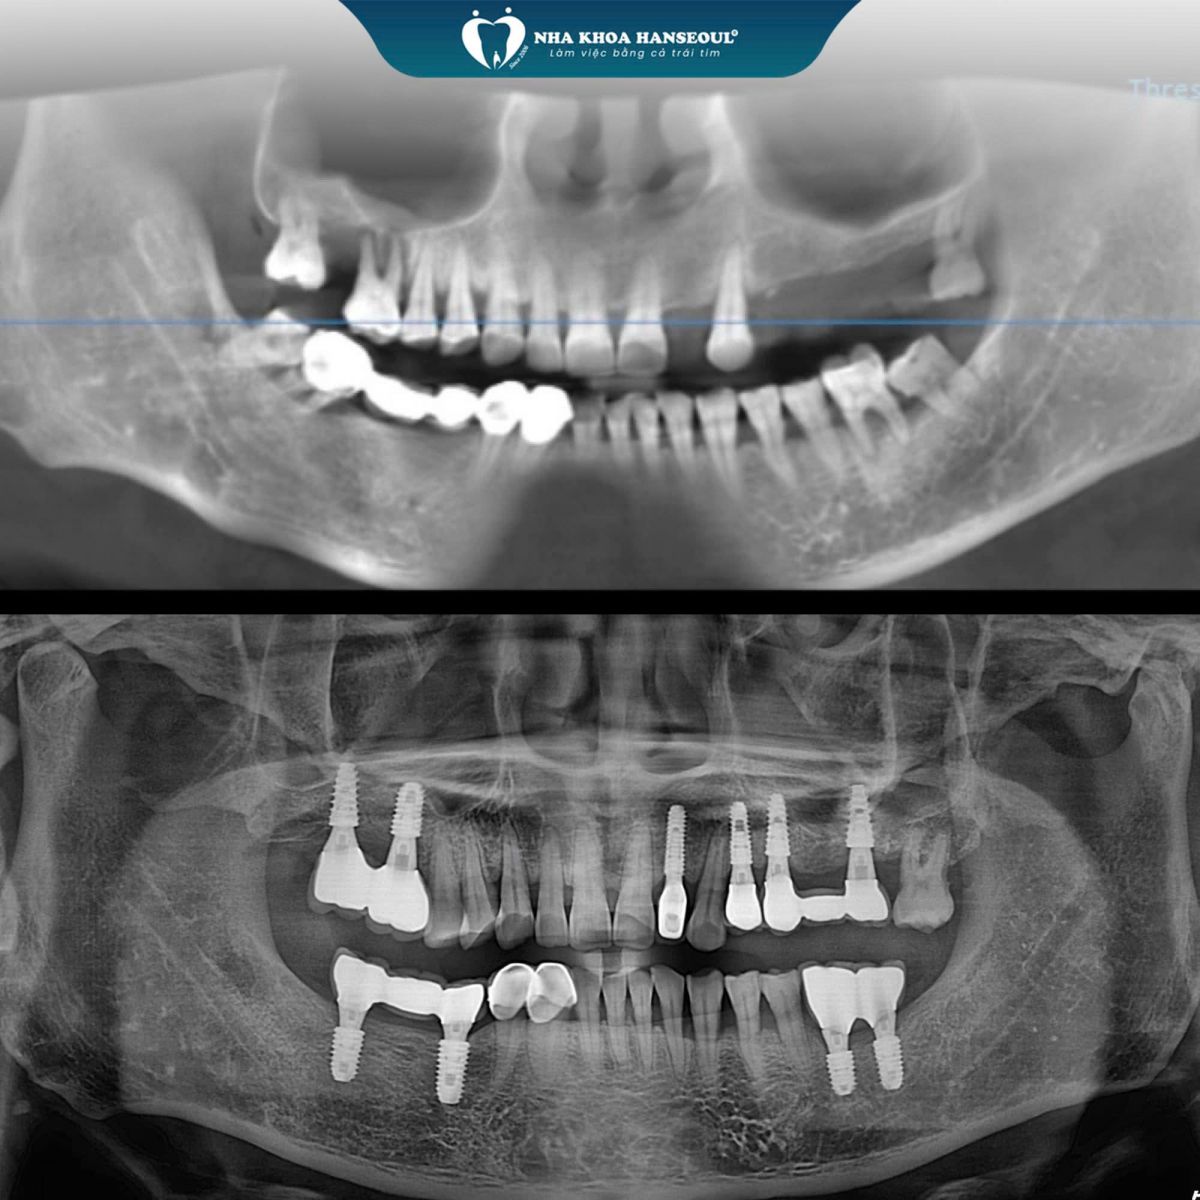

Các ca điều trị của bác sĩ